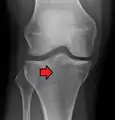

Subtle tibial plateau fracture on an AP X ray of the knee